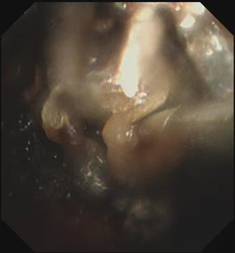

随着每一次精准夹取和冷冻操作,顽固的异物被一点点从狭窄的气道内剥离出来,堆积在一旁的痰痂、血痂和痰栓逐渐增多,堆积起来的长度居然达到了惊人的18厘米。

当最后一块异物被取出,患者的气管终于露出了原来的“庐山真面目”:

那堆长达18厘米的痰痂、血痂和痰栓不仅是这次急救成功的有力证明,也让人深感气道管理的重要性。